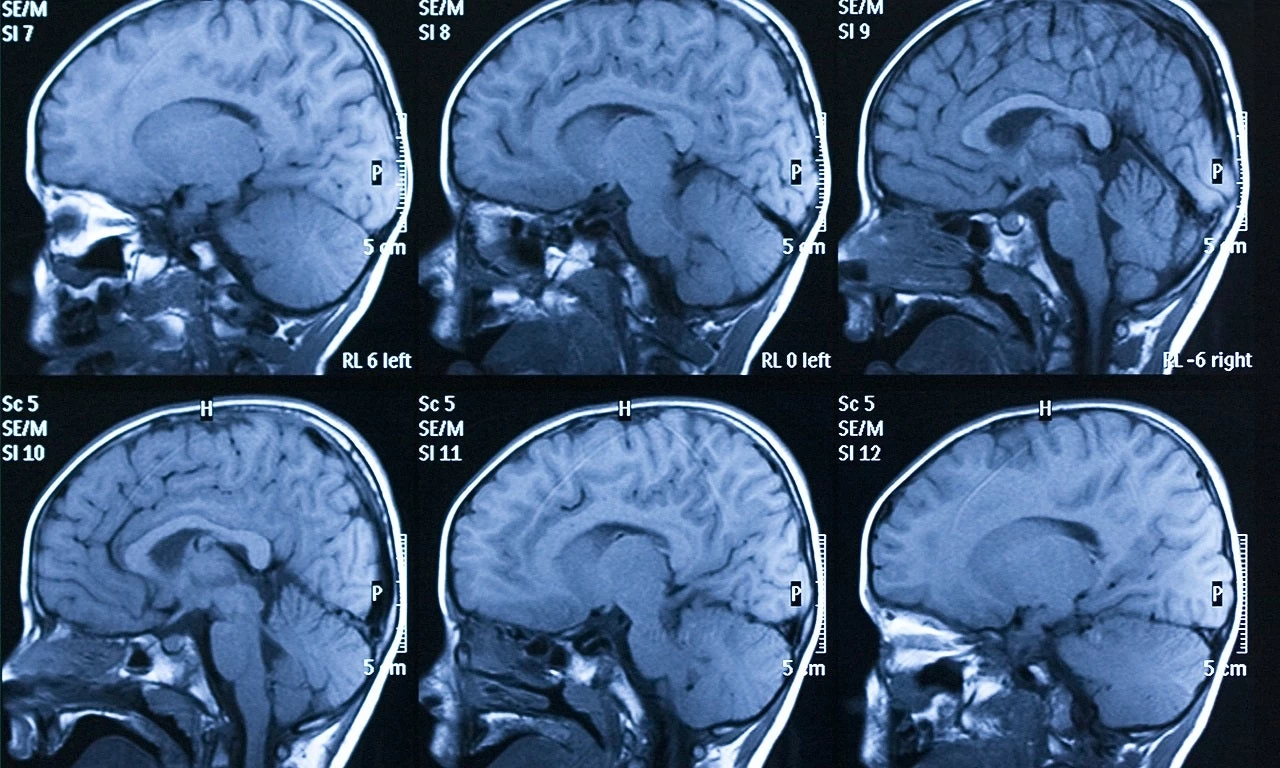

Η τεχνητή νοημοσύνη εντοπίζει τις εγκεφαλικές αιμορραγίες – Μεγάλη βοήθεια για τους ακτινολόγους

Έναν νέο αλγόριθμο τεχνητής νοημοσύνης, που τα καταφέρνει καλύτερα και από έμπειρους ακτινολόγους στην ανίχνευση μικρών εγκεφαλικών αιμορραγιών, ανέπτυξαν ερευνητές στις ΗΠΑ. Η εξέλιξ...